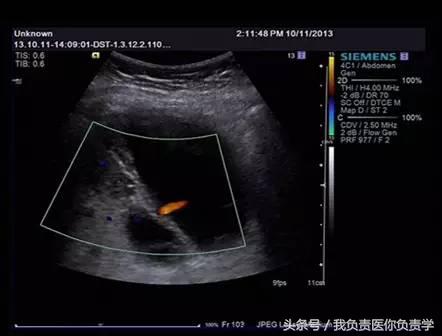

图3-图6示胆囊壁局部回声中断,探头加压及松开时CDFI可见红色及蓝色多普勒信号